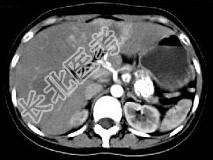

- 单项选择题根据所提供的图像,最可能的诊断为 ( )

A、胰尾囊腺癌肝转移

B、慢性胰腺炎

C、胰腺结核

D、胰岛细胞瘤

E、以上都不是